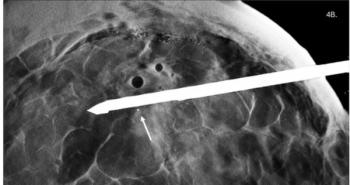

In recent years, investigators have been searching for a different brain imaging method that can side-step these problems and potentially provide better quality scans at the same time. Researchers from the University of Southern California Keck School of Medicine and California Institute of Technology recently succeeded. They’ve developed functional photoacoustic computed tomography (fPACT) – a technique that works by emitting a laser beam of light into the area being imaged.